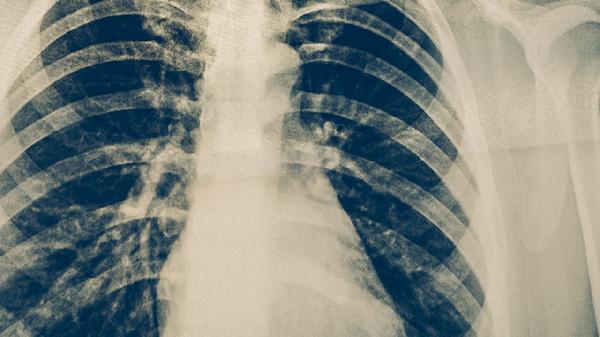

在恢复期,应避免剧烈运动,以免引发气道痉挛,推荐进行八段锦等温和的锻炼方式。饮食方面可以多吃银耳、百合等滋阴润肺的食物,避免辛辣和油炸食品。如果咳嗽持续超过一个月,或伴有喘鸣、胸痛等症状,应及时复查胸部X光片,排除黏膜持续受损或肺不张等并发症的可能。如果夜间咳嗽比较明显,可以尝试垫高枕头,减少对气道的刺激。